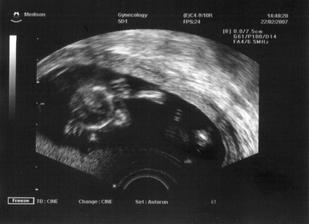

Jelikož se sen proměnil ve skutečnost, tak k nám přiletí čáp nebo vrána koncem velkých prázdnin 2007. Už jsem začali nakupovat, většinu věciček pro mimi kupuji v sekáči,jelikož se domnívám, že je úplná škoda utrácet penízky za nové oblečení,které je nekřesťansky drahé.Miminko stejně nic neunosí a ze všeho za chvíli vyroste.Takže si fakt vybírám a zatím se mi daří...Moc se těšíme...